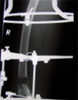

13 years old male chinese boy with knee deformity

Pre

Op

Sustained Salter type2 fracture distal femoral epiphysis which was treated with open reduction and Kwiring. Later resulted in eccenteric physeal arrest. Treated with Langenskoiid procedure but continued to develop shortening and valgus deformity knee